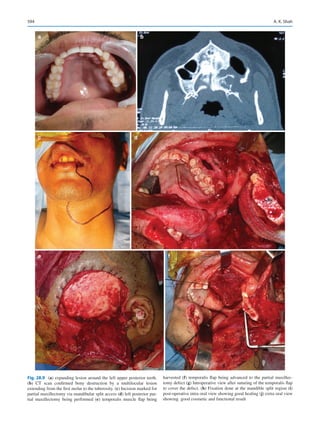

Principles of Surgical Management of Oral Cancer��������������������������������������������� 1869

Sushma Mehta and Moni Abraham Kuriakose